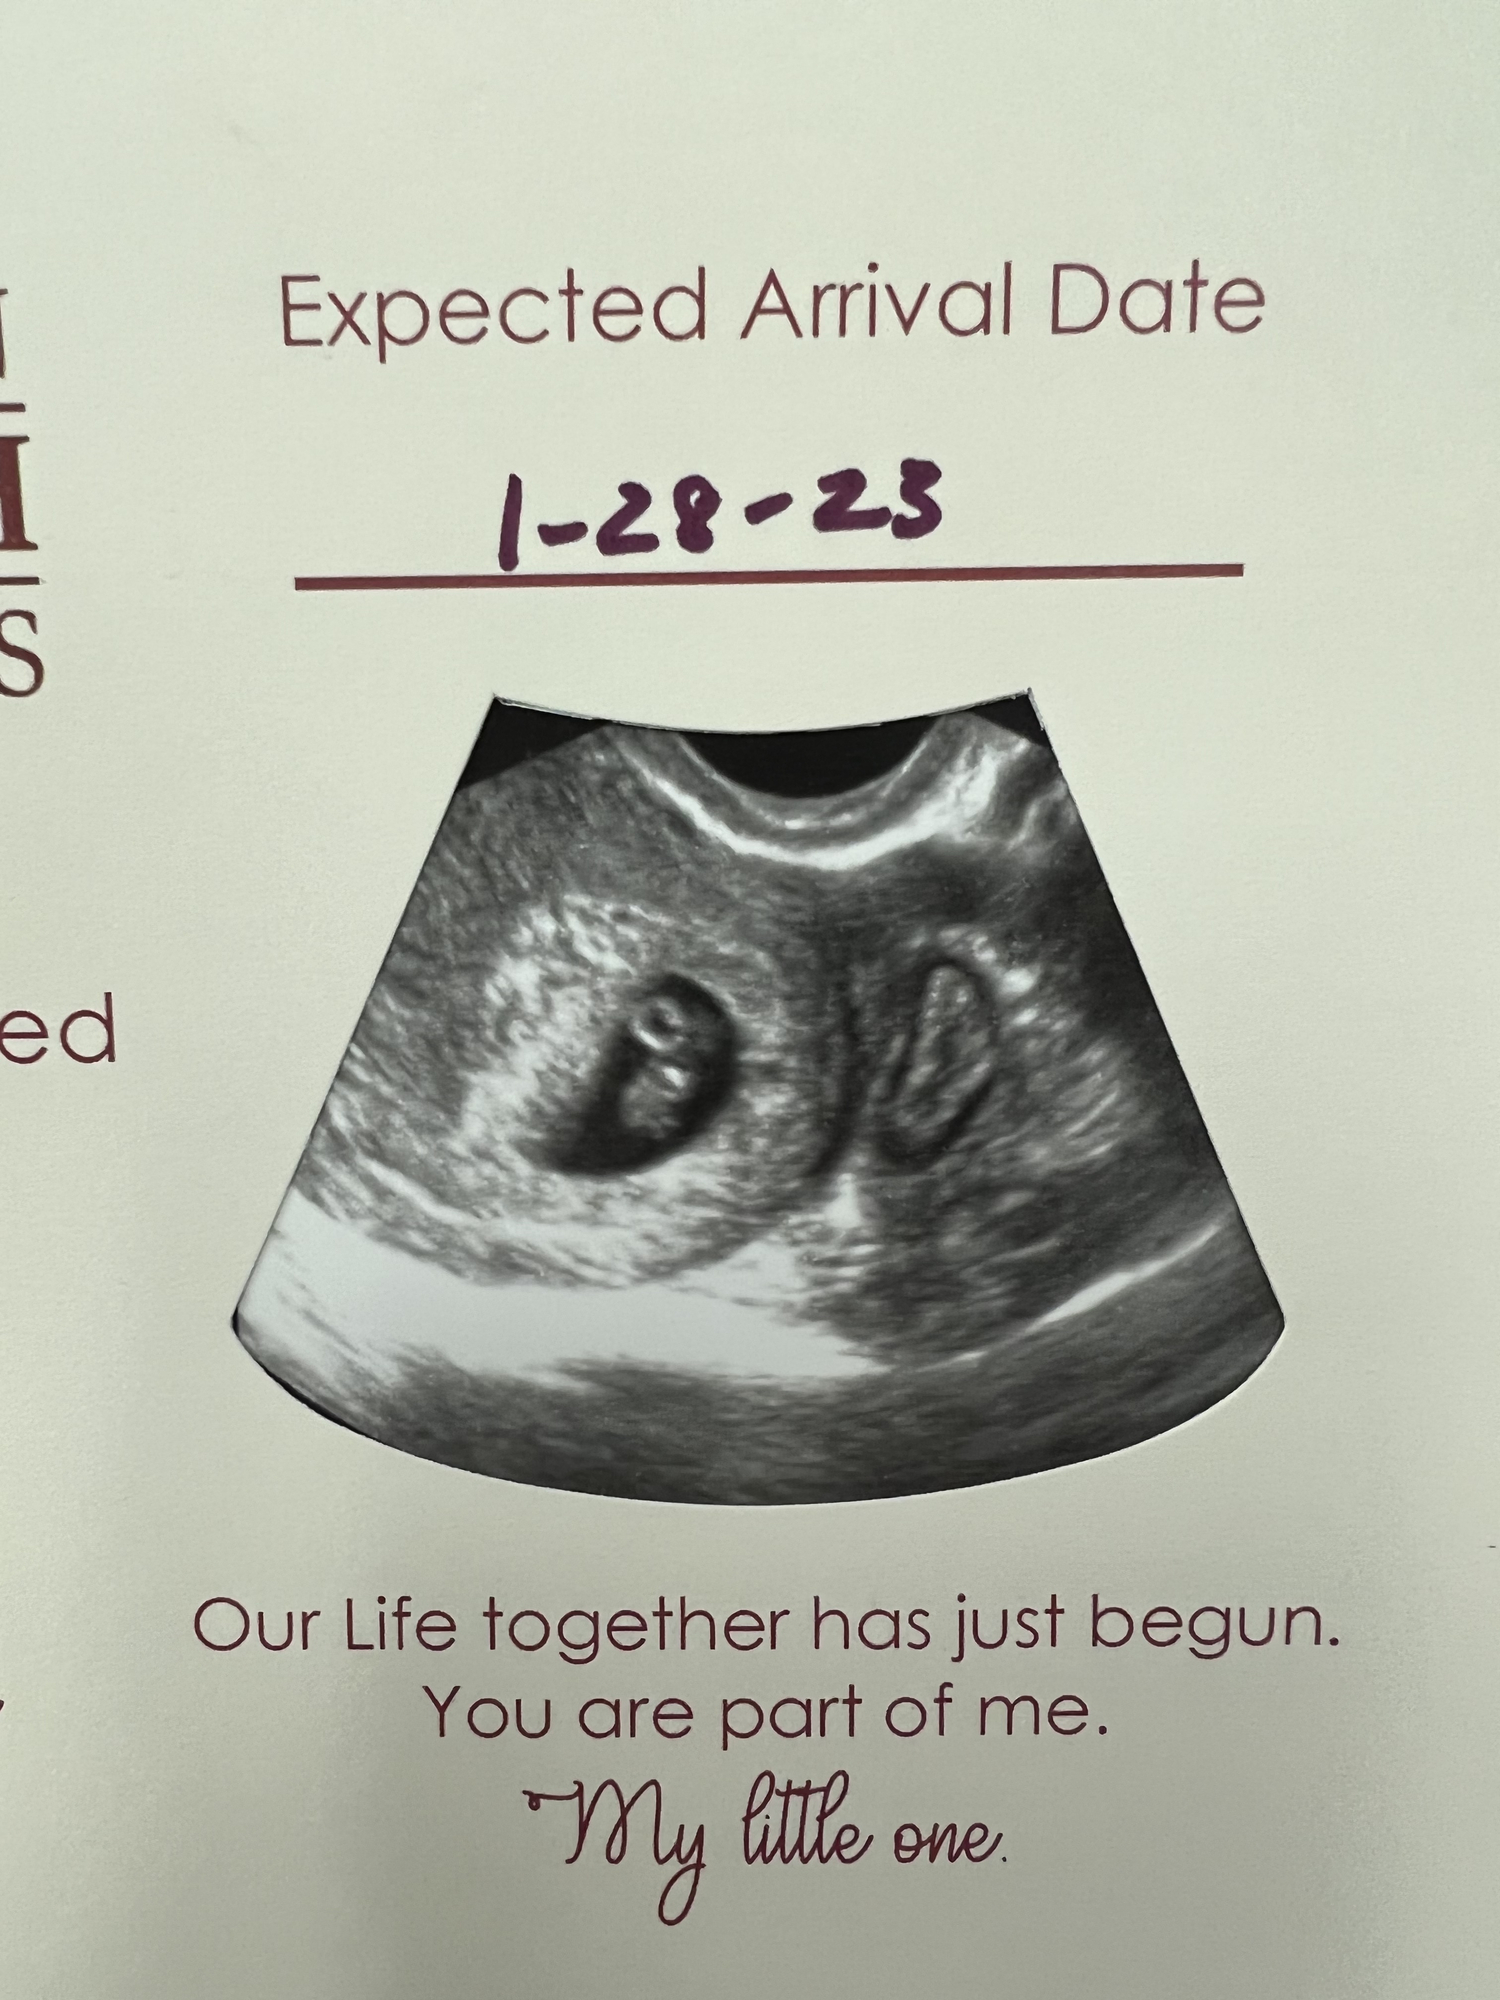

There’s a second thing that does not look like the other on my ultrasound. The left one they said is a baby, but what could the thing on the right be? I have another ultrasound in 2 weeks to find out what it is.

• My first thought was twins, but like the other poster, I'm not a US tech (and I would assume the US tech would've told you at the appt if it is twins). Keep us posted!

That’s kind of what it looks like to me, but they wouldn’t straight up say anything! Fingers crossed at the next appointment. They run in my husband’s family.